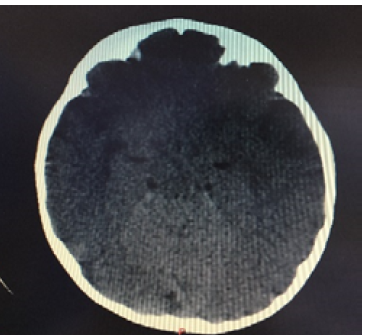

The child had normal neurodevelopmental history (no delay in milestones), vaccination history was up to date (according to his age). He presented with a history of somnolence, change in level of consciousness and high grade fever that developed progressively over the last three days. In the ED he was febrile, tachycardic, normotensive, and lethargic with hyperextended neck. His physical exam was significant for neck stiffness, normally reactive pupils, poorly responsive baby; his Glasgow Coma Scale was 11-12. Urgently first dose of Ceftriaxone, Vancomycin and Amikacin were given and CT brain done showing total enfacement of the brain tissue with no evidence of the sulcal pattern Figure 1, CRP was elevated associated with left shift leukocytosis. The patient was admitted to PICU, infectious disease specialist and neurologist were consulted, IV antibiotics meningeal dose continued, acyclovir added, lumbar puncture was contraindicated because of brain edema, methylprednisolone added to treatment. 48 hours after admission, clinical improvement started to show with reduced neck stiffness and slowly recovering mental status (he started to follow command by eye movements according to the corresponding direction with slight neck deviation, good muscle strength and slight improvement in swallowing). Repeated CT brain revealed a large area of focal hypo density involving the left fronto-parietal lobe and Sylvian fissure, focal densities were also noted involving the left thalamus and retro thalamic area with persistence of the effacement of the brain tissue and compression of the ventricular system, Mannitol was started and MRI brain was scheduled.

Figure 1: CT Scan of Brain Showing Total Enfacement of the Brain Tissue with no Evidence of the Sulcal Pattern